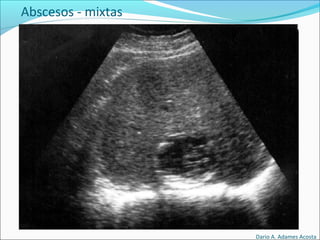

Lesiones básicas

Abscesos

Abscesos - mixtas

Dario A. Adames Acosta